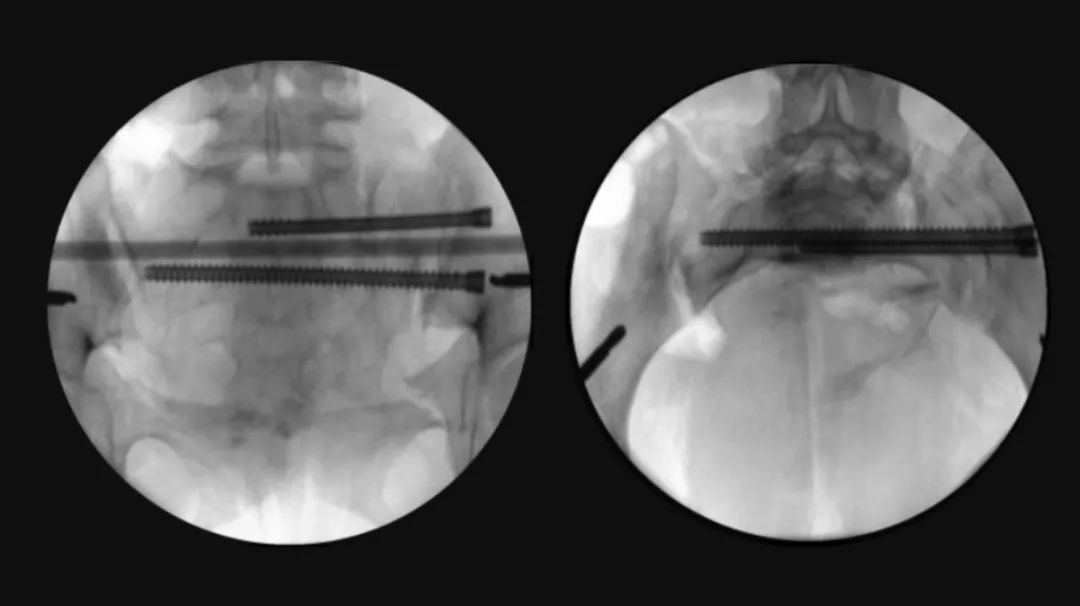

最后,手术团队利用智能化骨科手术机器人进行了螺钉通道及置入规划,并借助手持导向器,在实时动态三维可视化导航下,精准完成螺钉置入,完成了对该例骨盆骨折的微创治疗。

图六:螺钉置入规划、置入

术中透视验证螺钉置入效果

经过2个半小时的“数智化微创手术”,患者手术切口仅有5个,切口平均长度小于1cm,术中出血量仅有50cc,“真·微创”治疗效果着实令人满意。智能化骨科手术机器人真正实现了看得见的‘快准稳’,不仅让医生有了‘超级助手’,真正意义上实现骨盆骨折微创治疗,同时对患者康复和术后生活质量极为有利。

图七:患者术后三天影像资料